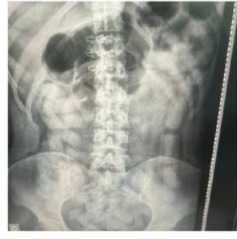

Ante la posibilidad de estar frente a «capsuleros» o «mulas», se procedió a dar intervención médica para realizar placas radiográficas a otros sospechosos.

El resultado de las radiografías confirmó el riesgo extremo al que se sometieron los involucrados: seis personas (cuatro mujeres y dos hombres) presentaban cuerpos extraños en sus organismos. Bajo estricta vigilancia médica, y tras los protocolos de expulsión, se contabilizaron 502 cápsulas de cocaína.